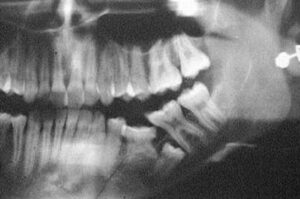

- mancanza di spazio che può portare ad Anchilosi (un’anomala immobilità, unione o fusione tra i denti e l’osso alveolare) o ad inclusione.

Infine c’è un tipo particolare di eruzione tardiva, chiamata eruzione ritardata passiva (terza dentizione). L’osso mandibolare o mascellare, al momento della nascita, si modifica per permettere la formazione degli alveoli dentali. Nell’anziano con la caduta dei denti e il riassorbimento dell’osso alveolare si può riscontrare il fenomeno dell’emersione, come dalla sabbia, di denti precedentemente inclusi, di cui il paziente si accorge per il disturbo che questi arrecano alle eventuali protesi. La soluzione, anche in questo caso, è togliere il dente.